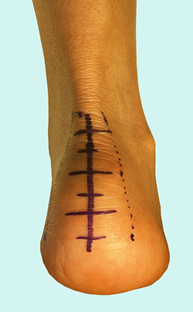

图9:开放性跟腱止点清理术手术切口示意图

图10:开放性跟腱止点清理术手术切口